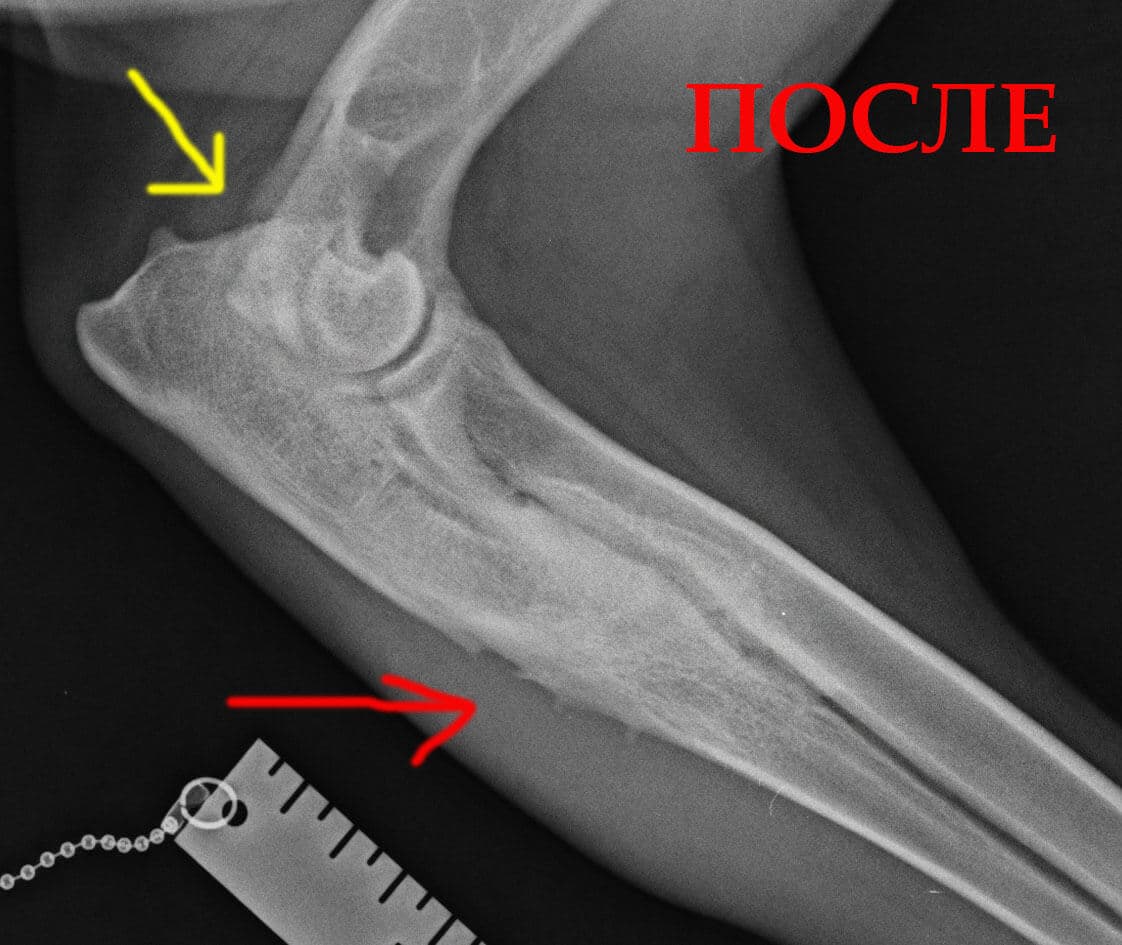

Контрольный рентгеновский снимок в возрасте 9 месяцев. Видно полное сращение крючковидного отростка и зоны распила.